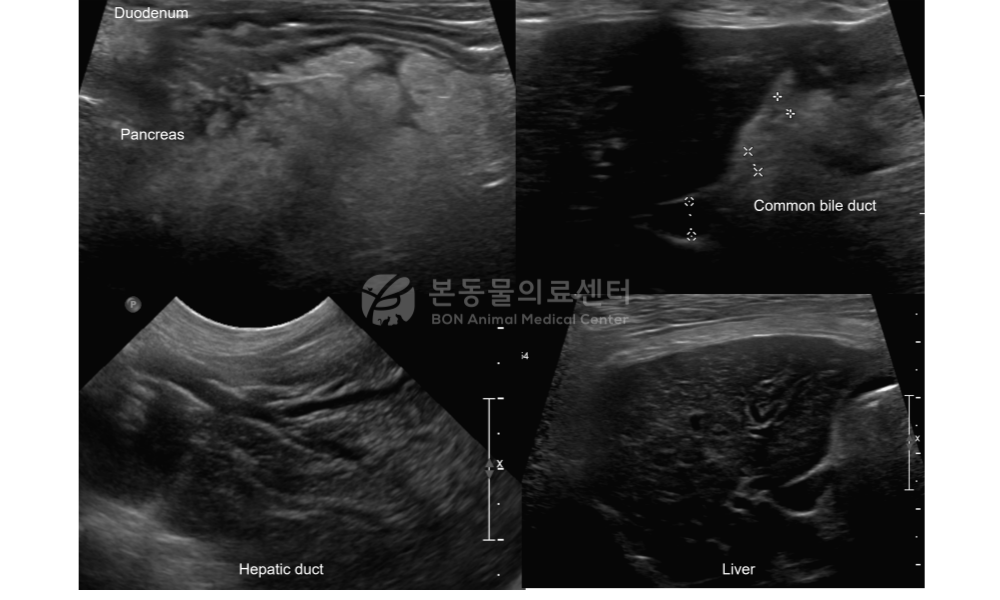

복부 초음파 검사 상 심한 췌장염 및 복막염, 십이지장 염증이 확인되며 이차적인 담도계 확장 (extrahepatic bile duct obstruction) 및 간 내 담도 확장과 간 실질의 이질적인 변화가 확인되어 간담도염 (cholangiohepatitis) 가능성도 고려됩니다.

[복부 초음파 검사]

검사 결과를 정리해 보면, 만성췌장염으로 관리 중인 환자에서 염증 수치 및 췌장염 지표가 상승했으며 복부초음파 검사에서 췌장염과 장염이 확인되었습니다. 혈액 검사에서는 고빌리루빈혈증과 요검사에서는 빌리루빈뇨가 관찰되었습니다. 추가로 복부초음파 상 담낭벽의 염증성 변화와 간외 담도의 확장, 부분 폐색 소견이 관찰되었습니다.

이에 대해 췌장염에 의한 이차적인 간외담관부분폐색, 상행감염으로 인한 담낭염, 이에 따른 담즙 정체로 유발된 간손상 및 간염이 환자의 현재 증상의 주된 원인으로 판단되었습니다.